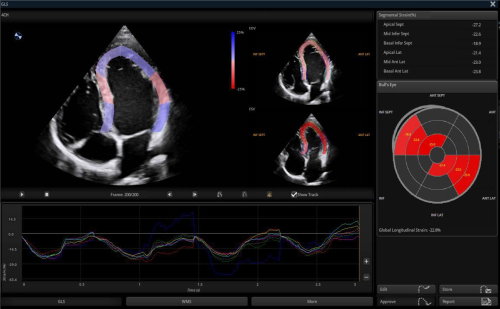

· Auto SG automatically traces and evaluates global and segmental myocardial motion, providing quantitative results for LV GLS and WMSI in a bull’s-eye diagram and curves for assessment.